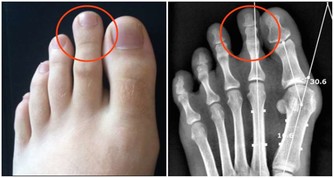

1、引發頸椎病

經常久坐的人,患上頸椎病的概率會更高。因為人體的骨連接需要足夠的黏液,來保證關節的正常使用。而久坐的人產生的黏液較少,會使骨關節變得乾燥,久而久之會引發頸椎病和關節炎。

此外,長時間保持一個姿勢不動,還會對頸椎動脈供血造成影響,並破壞人體正常生理彎曲,導致駝背和骨質增生。